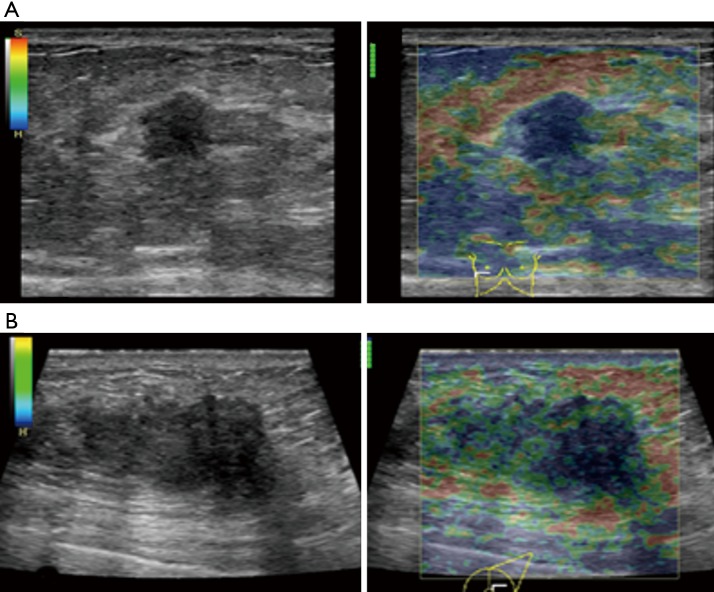

The average score of SE in visual examination of lesions was 4.28±0.67 points, and 36 lesions (36/40, 90%) scored above 4 points. It indicated that most tumors had relatively hard internal components. The reason was locally middle and late stage tumors produced more abnormal fibrous tissues for interstitial reaction. It leaded to the hardening of tumor texture (30). Moreover, the uneven distribution of hardness inside the tumor might be due to the large size of the malignant tumor and the uneven and disorderly distribution of its internal components, including necrosis, tumor cells and fibrous foci. The areas with more fibrous components were hard and the areas with more cellular components were soft (Figure 5).

Figure 5.

Comparison of elastography in 2 cases with different sizes of locally advanced invasive ductal carcinoma. (A) Female, 59 years old, tumor size was 1.31 cm × 1.25 cm × 1.74 cm (TD × APD × ULD) in the right breast. This was a double-contrast image of SE imaging. The elastic distribution in the lesion was relatively uniform. The visual score was 4 points in blue (hard). (B) Female, 44 years old, tumor size was 3.69 cm × 2.16 cm × 3.23 cm (TD × APD × ULD) in the left breast. This was a double-contrast image of SE imaging. The distribution of elasticity in the lesion was uneven, showing blue and green (moderate hardness). The visual score is 3 points. TD, transverse diameter (cm); APD, anteroposterior diameter (cm); ULD, upper and lower diameter (cm).